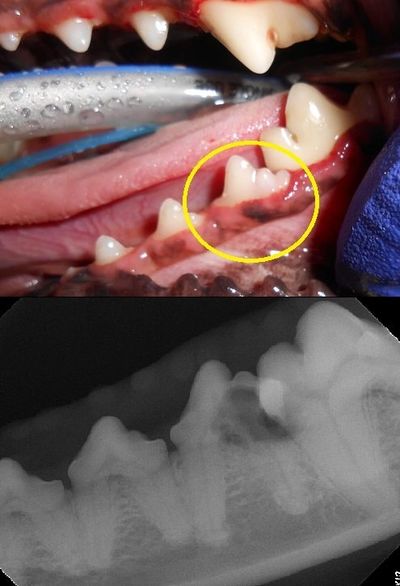

Dental tartar is a form of hardened dental plaque. It is caused by the continual accumulation of minerals from saliva on plaque on the teeth. Once tartar forms, it becomes very difficult to remove. If tartar forms at the gum line, it eventually leads to inflammation and progressive gum disease. It left untreated, it leads to a more serious form of gum disease called periodontitis. Pockets of bacteria get trapped beneath the gums eventually leading to bone and tissue loss that holds the teeth in place. This eventually leads to tooth loss and secondary disease that can spread to the heart, liver, and kidneys.

At Culver Pet Clinic, all professional dental cleanings are performed under general anesthesia. Don't be fooled by a non-anesthetic dental. It is impossible to be able to clean above the gum line on a pet that is awake and sometimes improperly restrained which can lead to injury of your pet. We take all precautions pertaining to general anesthesia. It is mandatory that all pets have a full physical examination and blood work prior to the dental. On the day of the procedure, an intravenous catheter is placed and fluids are administered. Monitoring is performed by the veterinarian or registered veterinary technician (RVT) as well with equipment to measure EKG, blood pressure, heart rate, CO2 levels, and body temperature. Your pet is never left unattended until they are completely recovered. Digital radiographs are taken to ensure proper assessment of your pet's mouth. Your pet is sent home with before and after photos of their teeth, copy of their radiographs, and a chart with full explanation of their teeth.